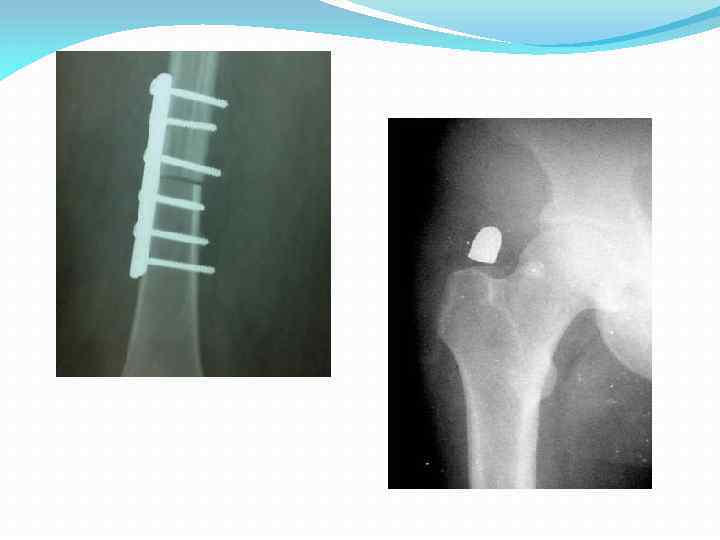

Викарная гипертрофия правой почки на фоне атрофии левой.